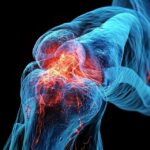

As duas condições causam dor e rigidez nas articulações. Mas você sabe quais são as diferenças entre artrite e artrose? Saiba então como diferenciar essas doenças.

A artrite e a artrose são os dois tipos mais comuns de doença articular. A inflamação nas articulações está presente em ambos os casos, mas existem algumas diferenças que podem te ajudar a identificar qual tipo de artrite você tem.

Embora muitos sintomas sejam bem parecidos, existem algumas particularidades nos sinais da artrite e da artrose.